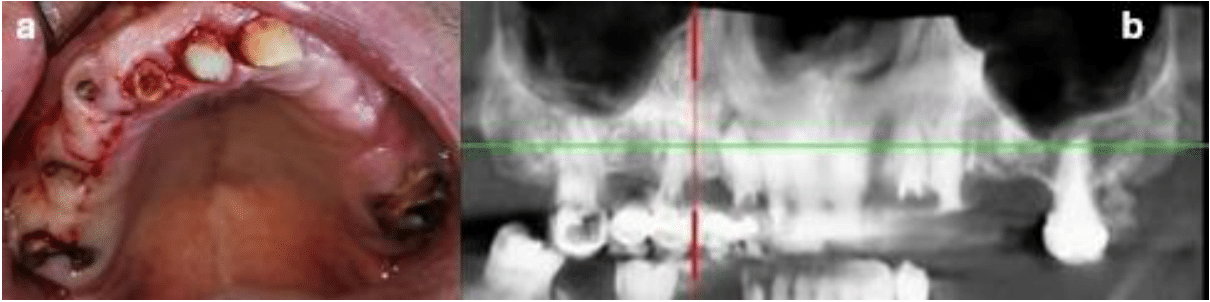

After clinical and radiographic examinations, treatment of the upper maxilla with a full-arch implant prosthesis with immediate provisional prosthesis was proposed (Figure 1a-b).

Figure 1a) Buccal view of the maxilla after removal of the non-retentive bridge,

b) Panoramic view of the residual teeth.